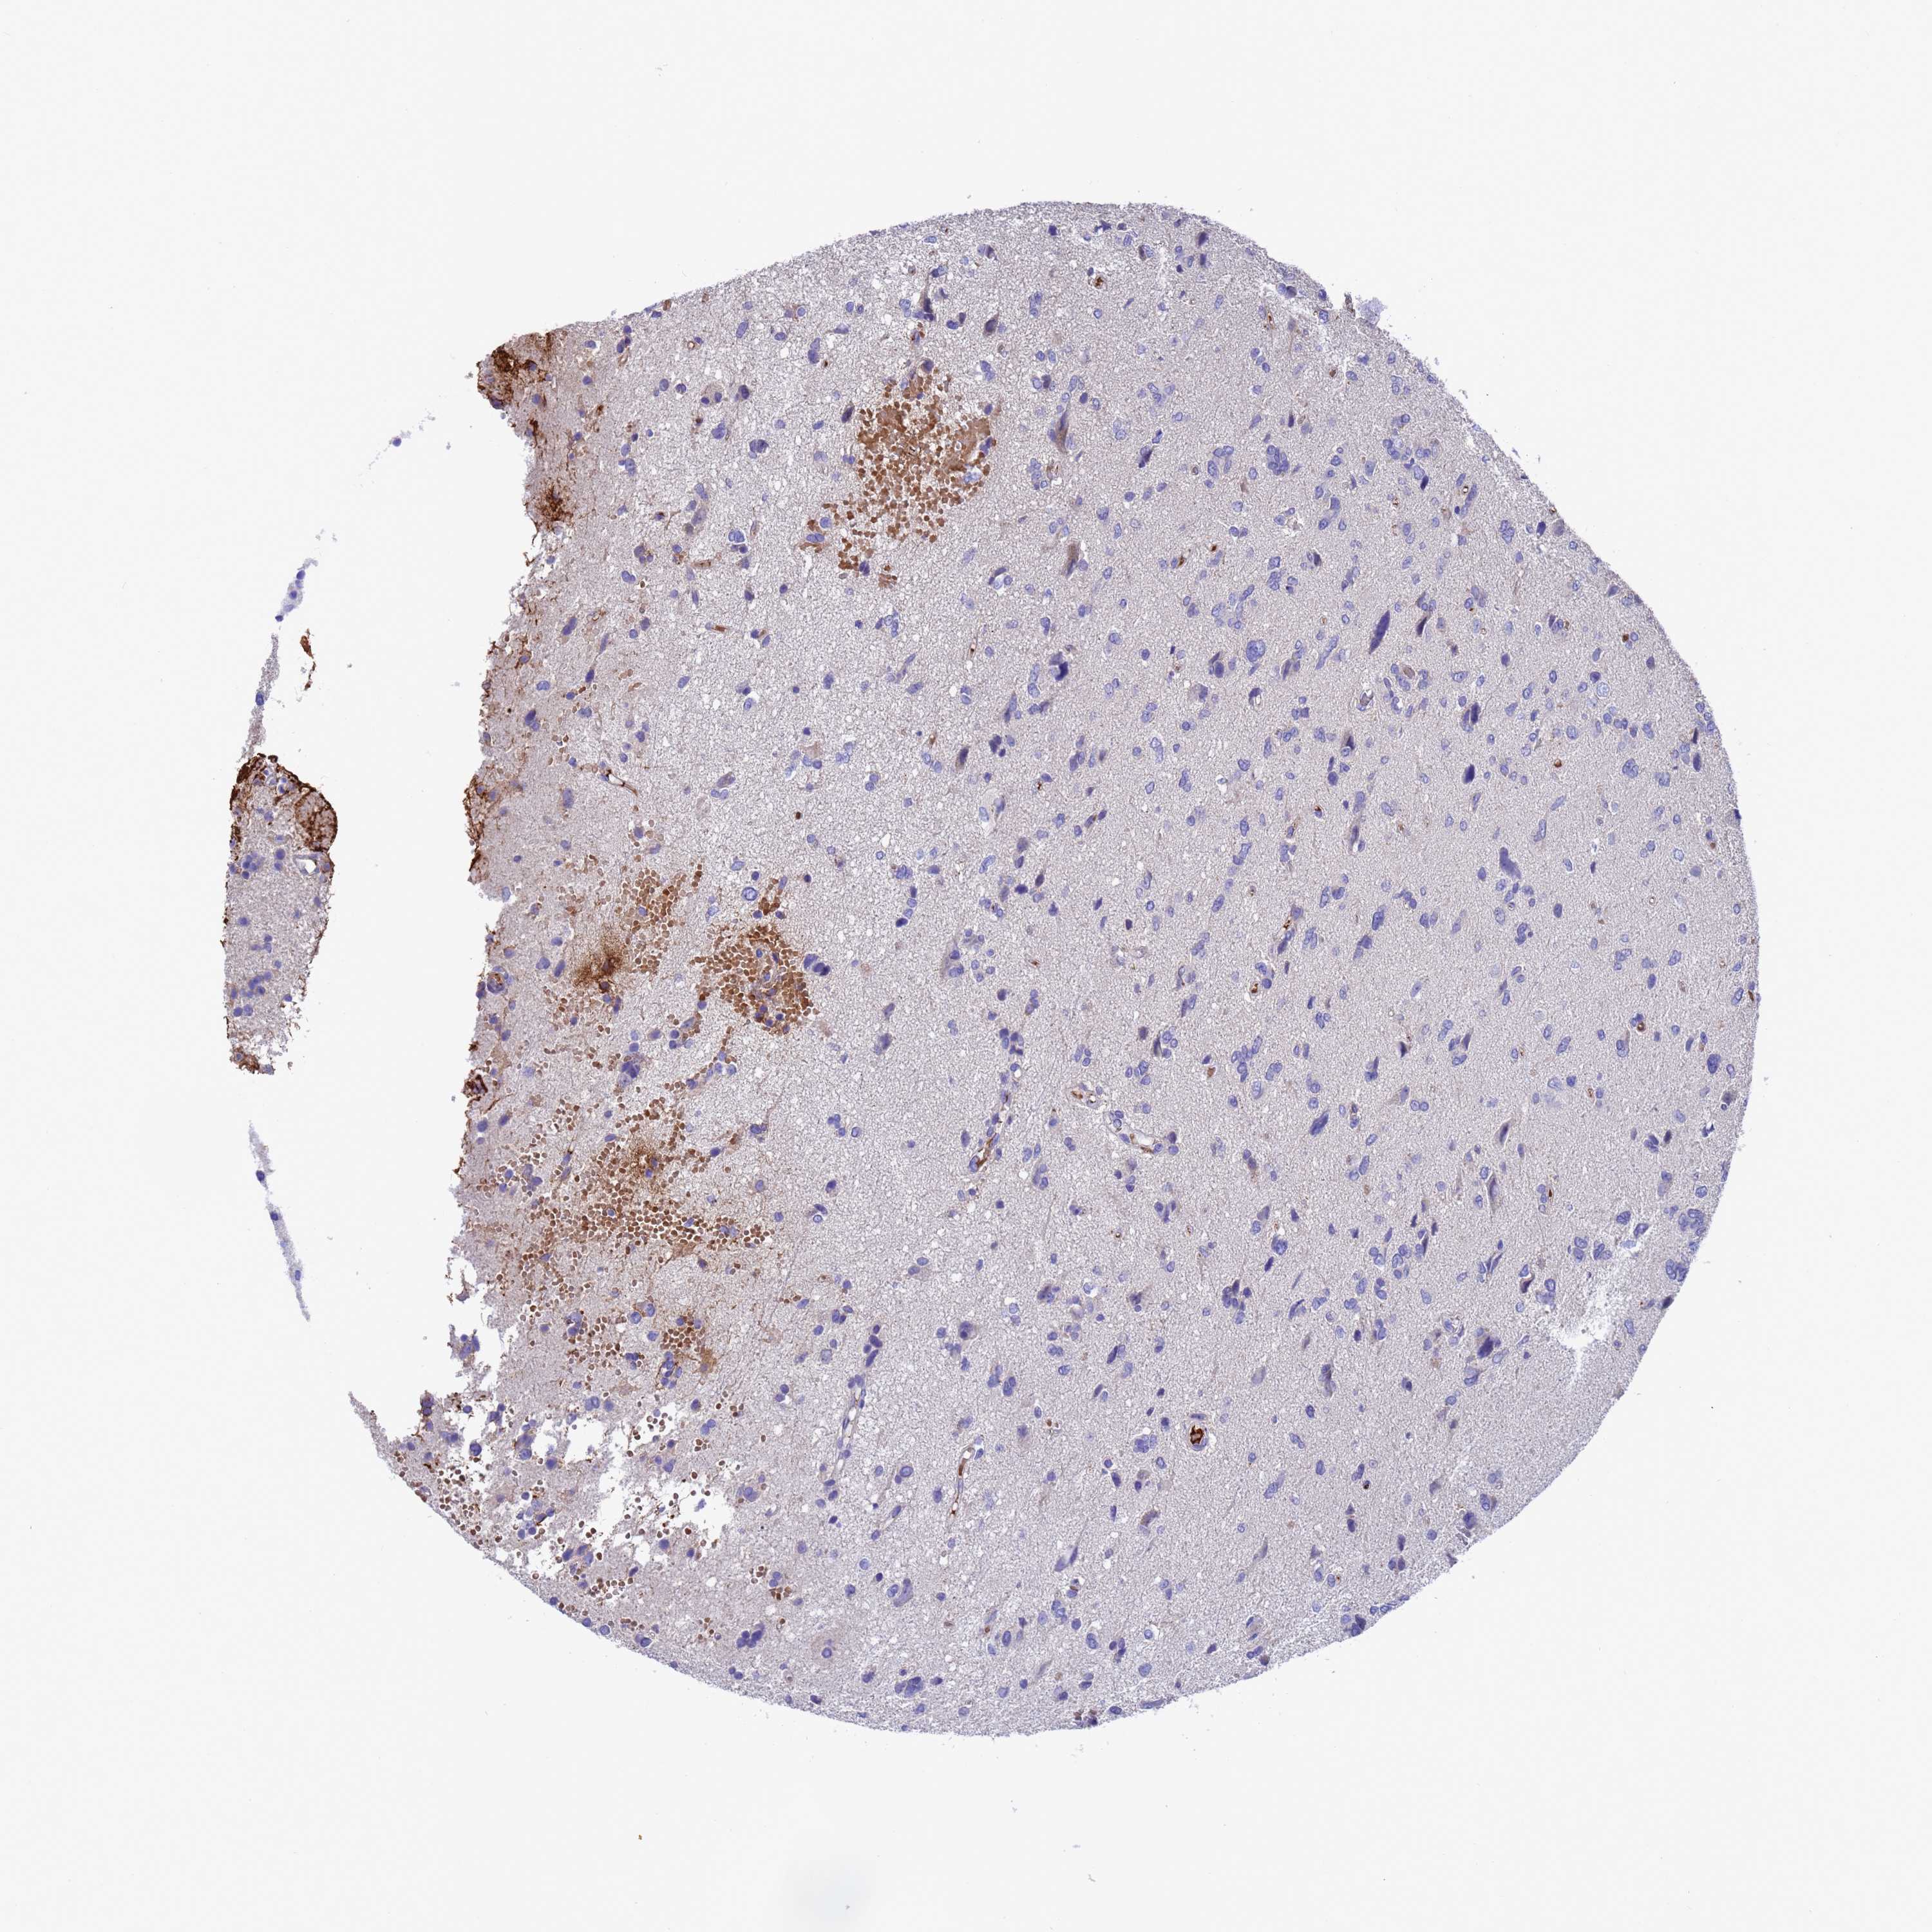

GLIOMA - Protein expressioni

A mouse-over function shows sample information and annotation data. Click on an image to view it in a full screen mode. Samples can be filtered based on level of antibody staining by selecting one or several of the following categories: high, medium, low and not detected. The assay and annotation is described here.

Note that samples used for immunohistochemistry by the Human Protein Atlas do not correspond to samples in the TCGA dataset.

Antibody stainingi

Antibody staining in the annotated cell types in the current human tissue is reported as not detected, low, medium, or high, based on conventional immunohistochemistry profiling in selected tissues. This score is based on the combination of the staining intensity and fraction of stained cells.

Each image is clickable and will lead to virtual microscopy that enables deeper exploration of all samples and also displays staining intensity scores, fraction scores and subcellular localization as well as patient and tissue information for each sample.

Antibody HPA046358

Staining

High

Medium

Low

Not detected

Intensity

Strong

Moderate

Weak

Negative

Quantity

>75%

75%-25%

<25%

None

Location

Nuclear

Cytoplasmic/membranous

Cytoplasmic/membranous,nuclear

Glioma, malignant, High grade

Glioma, malignant, Low grade

Glioblastoma, NOS